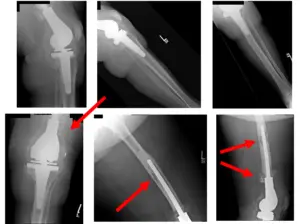

Pre-Surgical X-Rays show left TKA dislocation with dorsal translation of the tibia and widening of the tibiofemoral joint

Intraoperative Fluoroscopy Images

X-Rays show left knee TKA one year post-operatively

Upon follow-up patient complains of no pain, has a good range of motion, is weight-bearing as tolerated, and has been doing well subsequently.